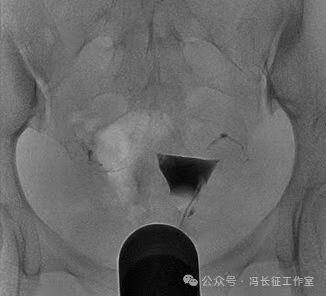

栓塞术后7个月于2015年1月做子宫输卵管造影复查看看栓塞效果

平片显示盆腔内2个C形高密度影为弹簧圈

造影显示2个弹簧圈紧实固定在输卵管间质部和峡部近段。弹簧圈两端由于弹性回缩力的回缩呈C形,卡在输卵管内壁上,完全封闭管腔,造影剂未能进入通过栓塞段,栓塞段输卵管远端未能显影。